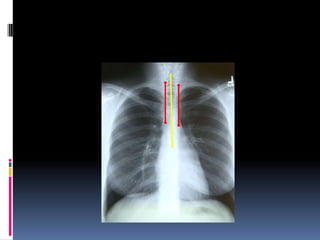

Positioning / Rotation

Does the thoracic spine align in the center of the

sternum and between the clavicles?

Clavicles – equidistant from spine

Positioning / Rotation Doesthe thoracic spine align in the center of the sternum and between the clavicles? Clavicles – equidistant from spine